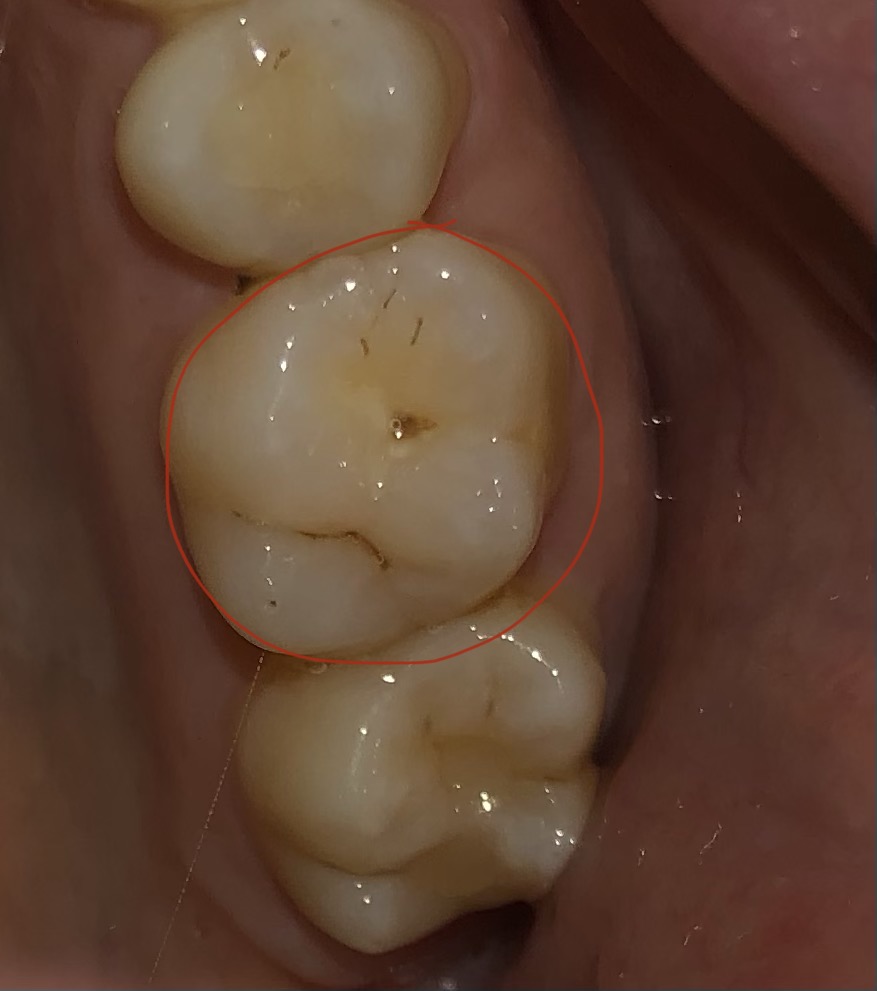

Gaatje over het hoofd gezien?

Al sinds langere tijd heb ik last van pijnklachten. Bij de kies was er niks op te merken. Nu is er inmiddels een breuk zichtbaar in de kies.

Is er een mogelijkheid dat de tandarts het gaatje heeft gemist? En nu dit niet behandeld is er uiteindelijk een breuk is ontstaan?